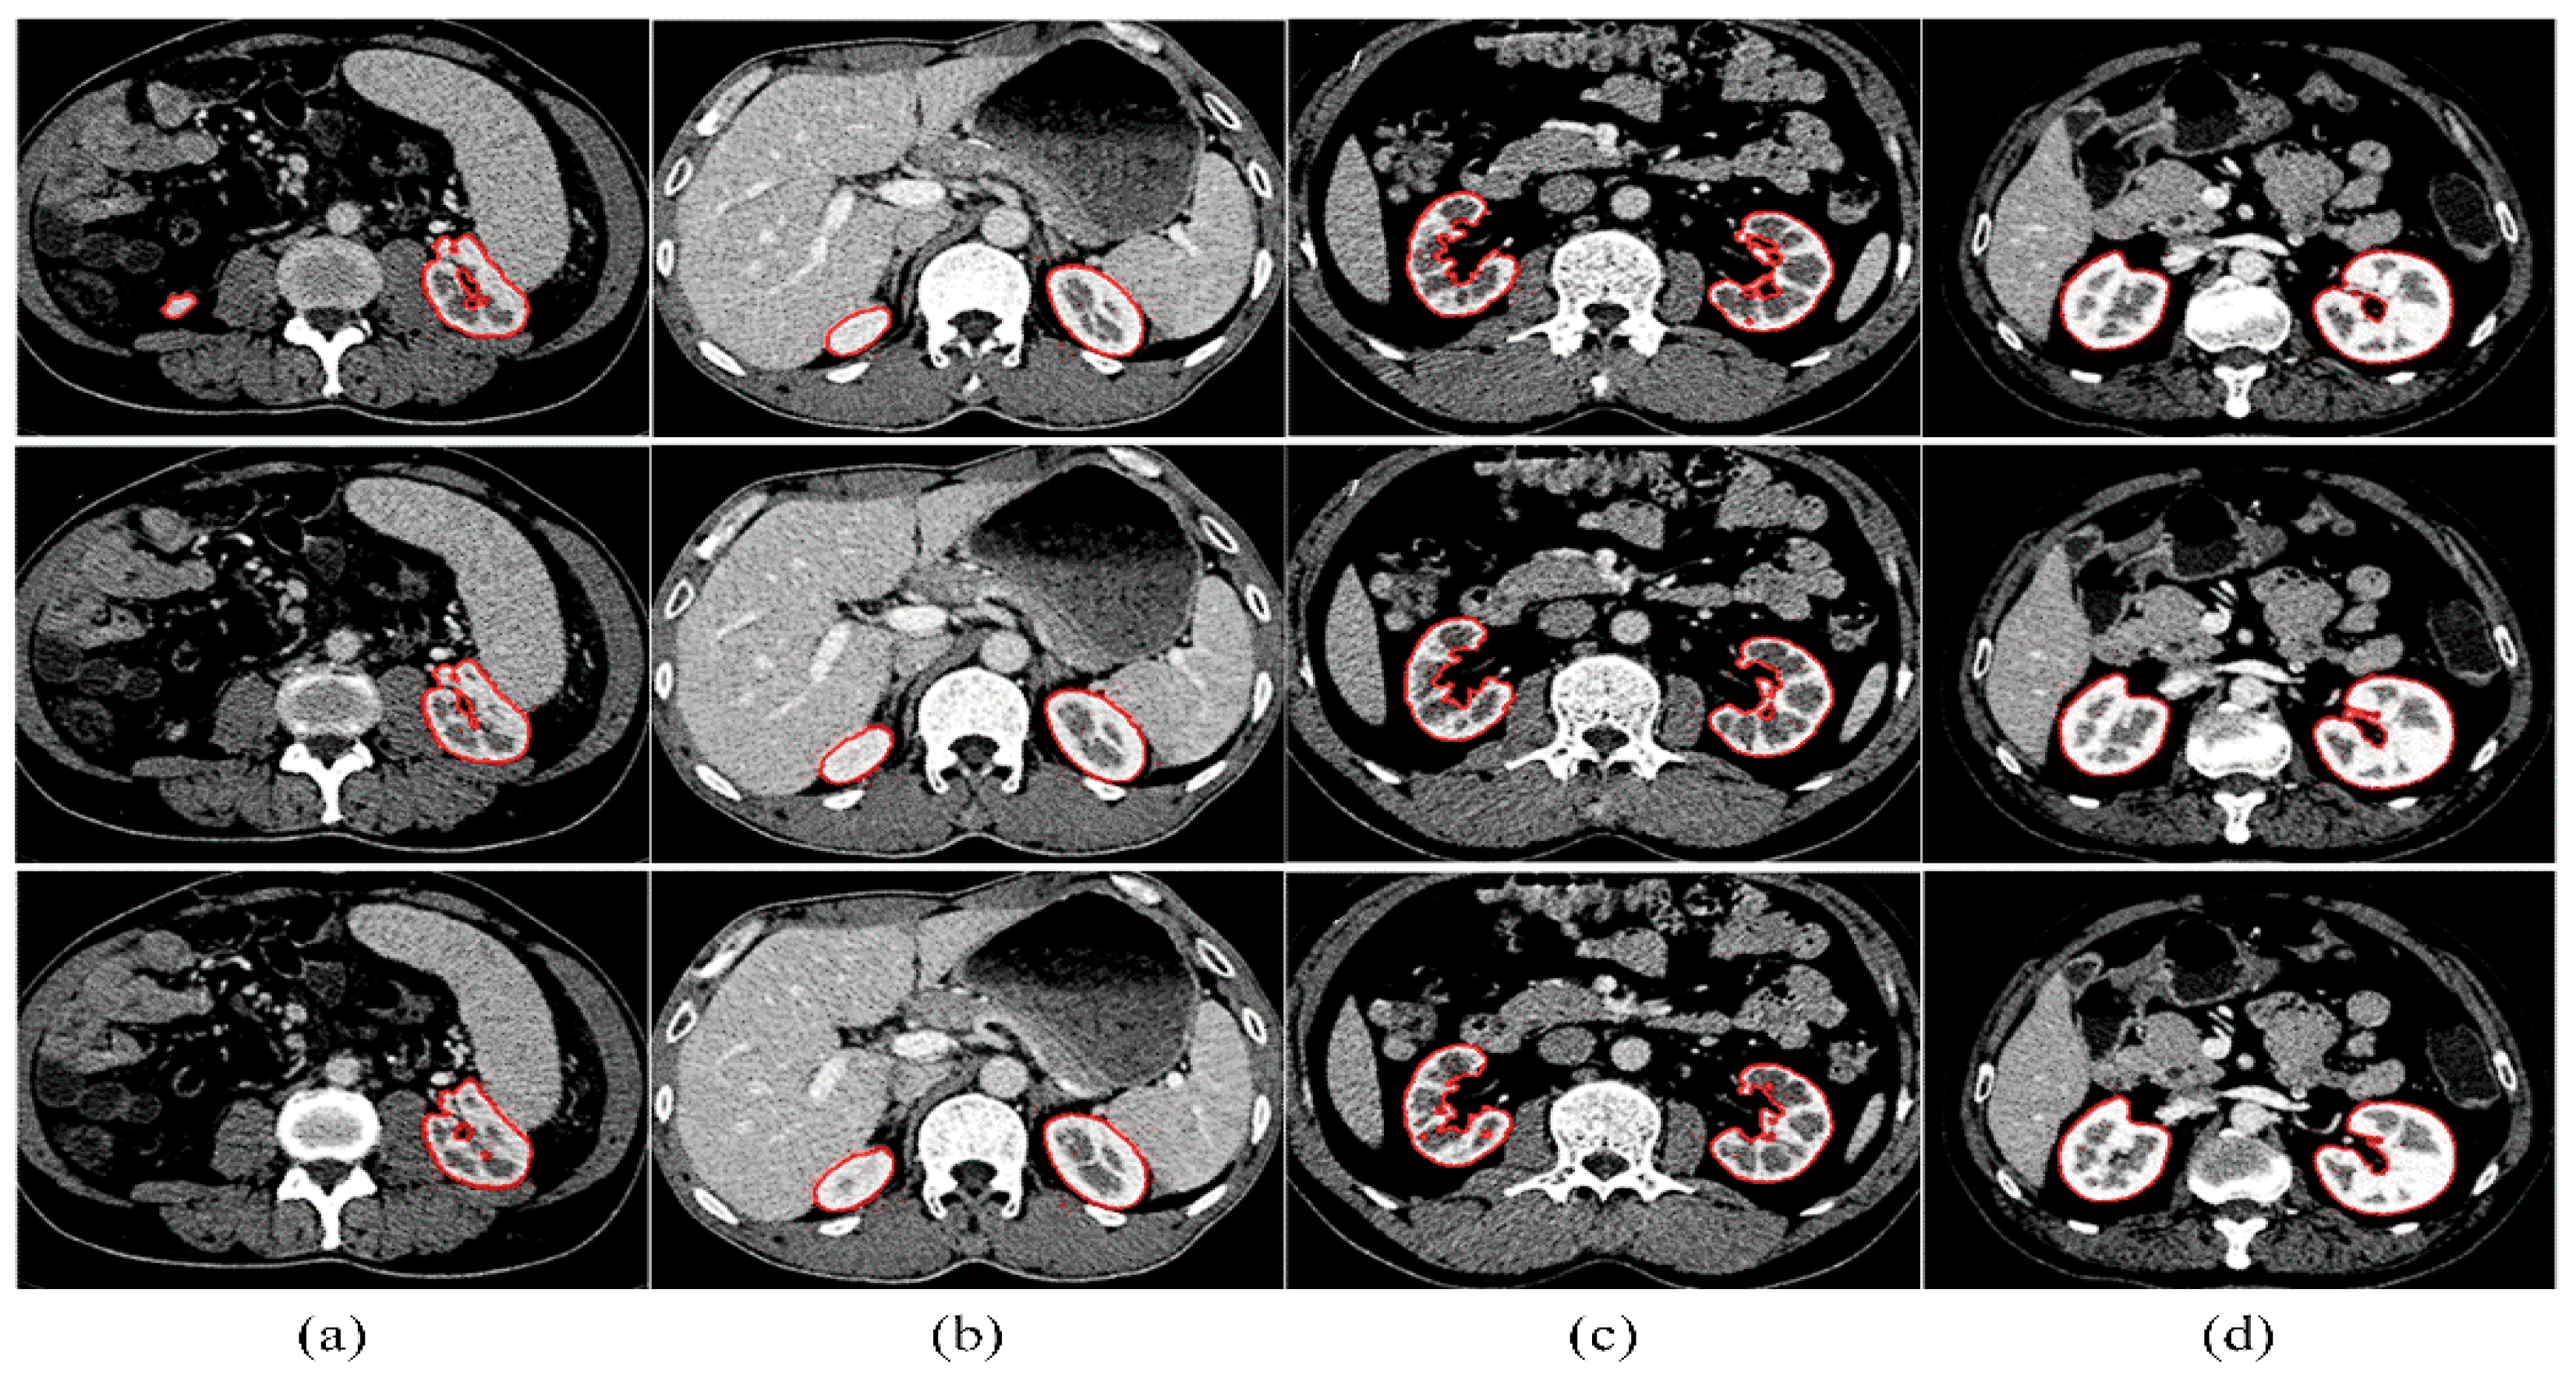

The kidney is surrounded by various tissues and organs, such as the spleen, muscle, spine, blood vessels, and others, and its grayscale is similar to that of the surrounding tissue. Figure 12a–d displays the results of three consecutive slices from four different sequences, respectively. The red curve represents the segmentation contour of the kidney. Despite the challenges posed by the adjacent tissues and organs, our kidney segmentation method is able to achieve desirable results. Moreover, it is reasonable to begin with the initial slice and proceed to segment all the slices in a volume in sequence.

Figure 12. (ad) Results of three consecutive slices from four sequences, respectively. The red curve represents the segmentation contour of the kidney.